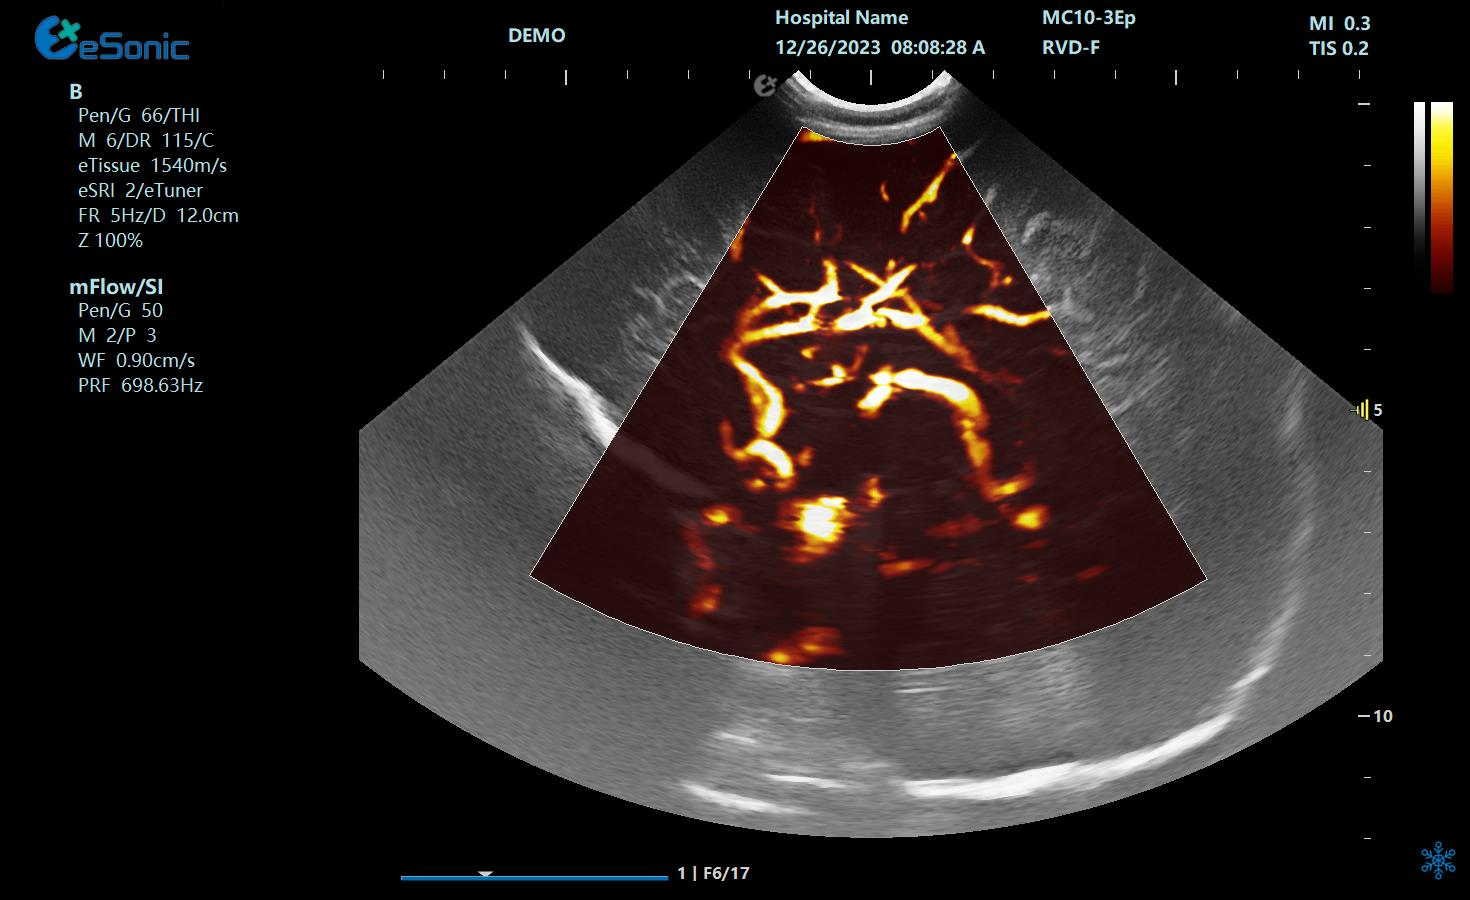

mFlow微血流显像技术,细节分辨率达100μm,支持频谱多普勒及VI血管指数定量。

mFlow新生儿颅脑

mFlow肾移植术后评估